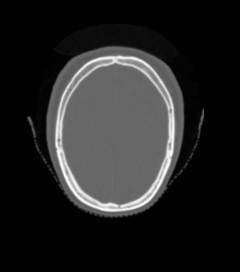

🔬 Medical Imaging Modalities

Eight different medical imaging modalities supported by UniMedVL

CT Scan